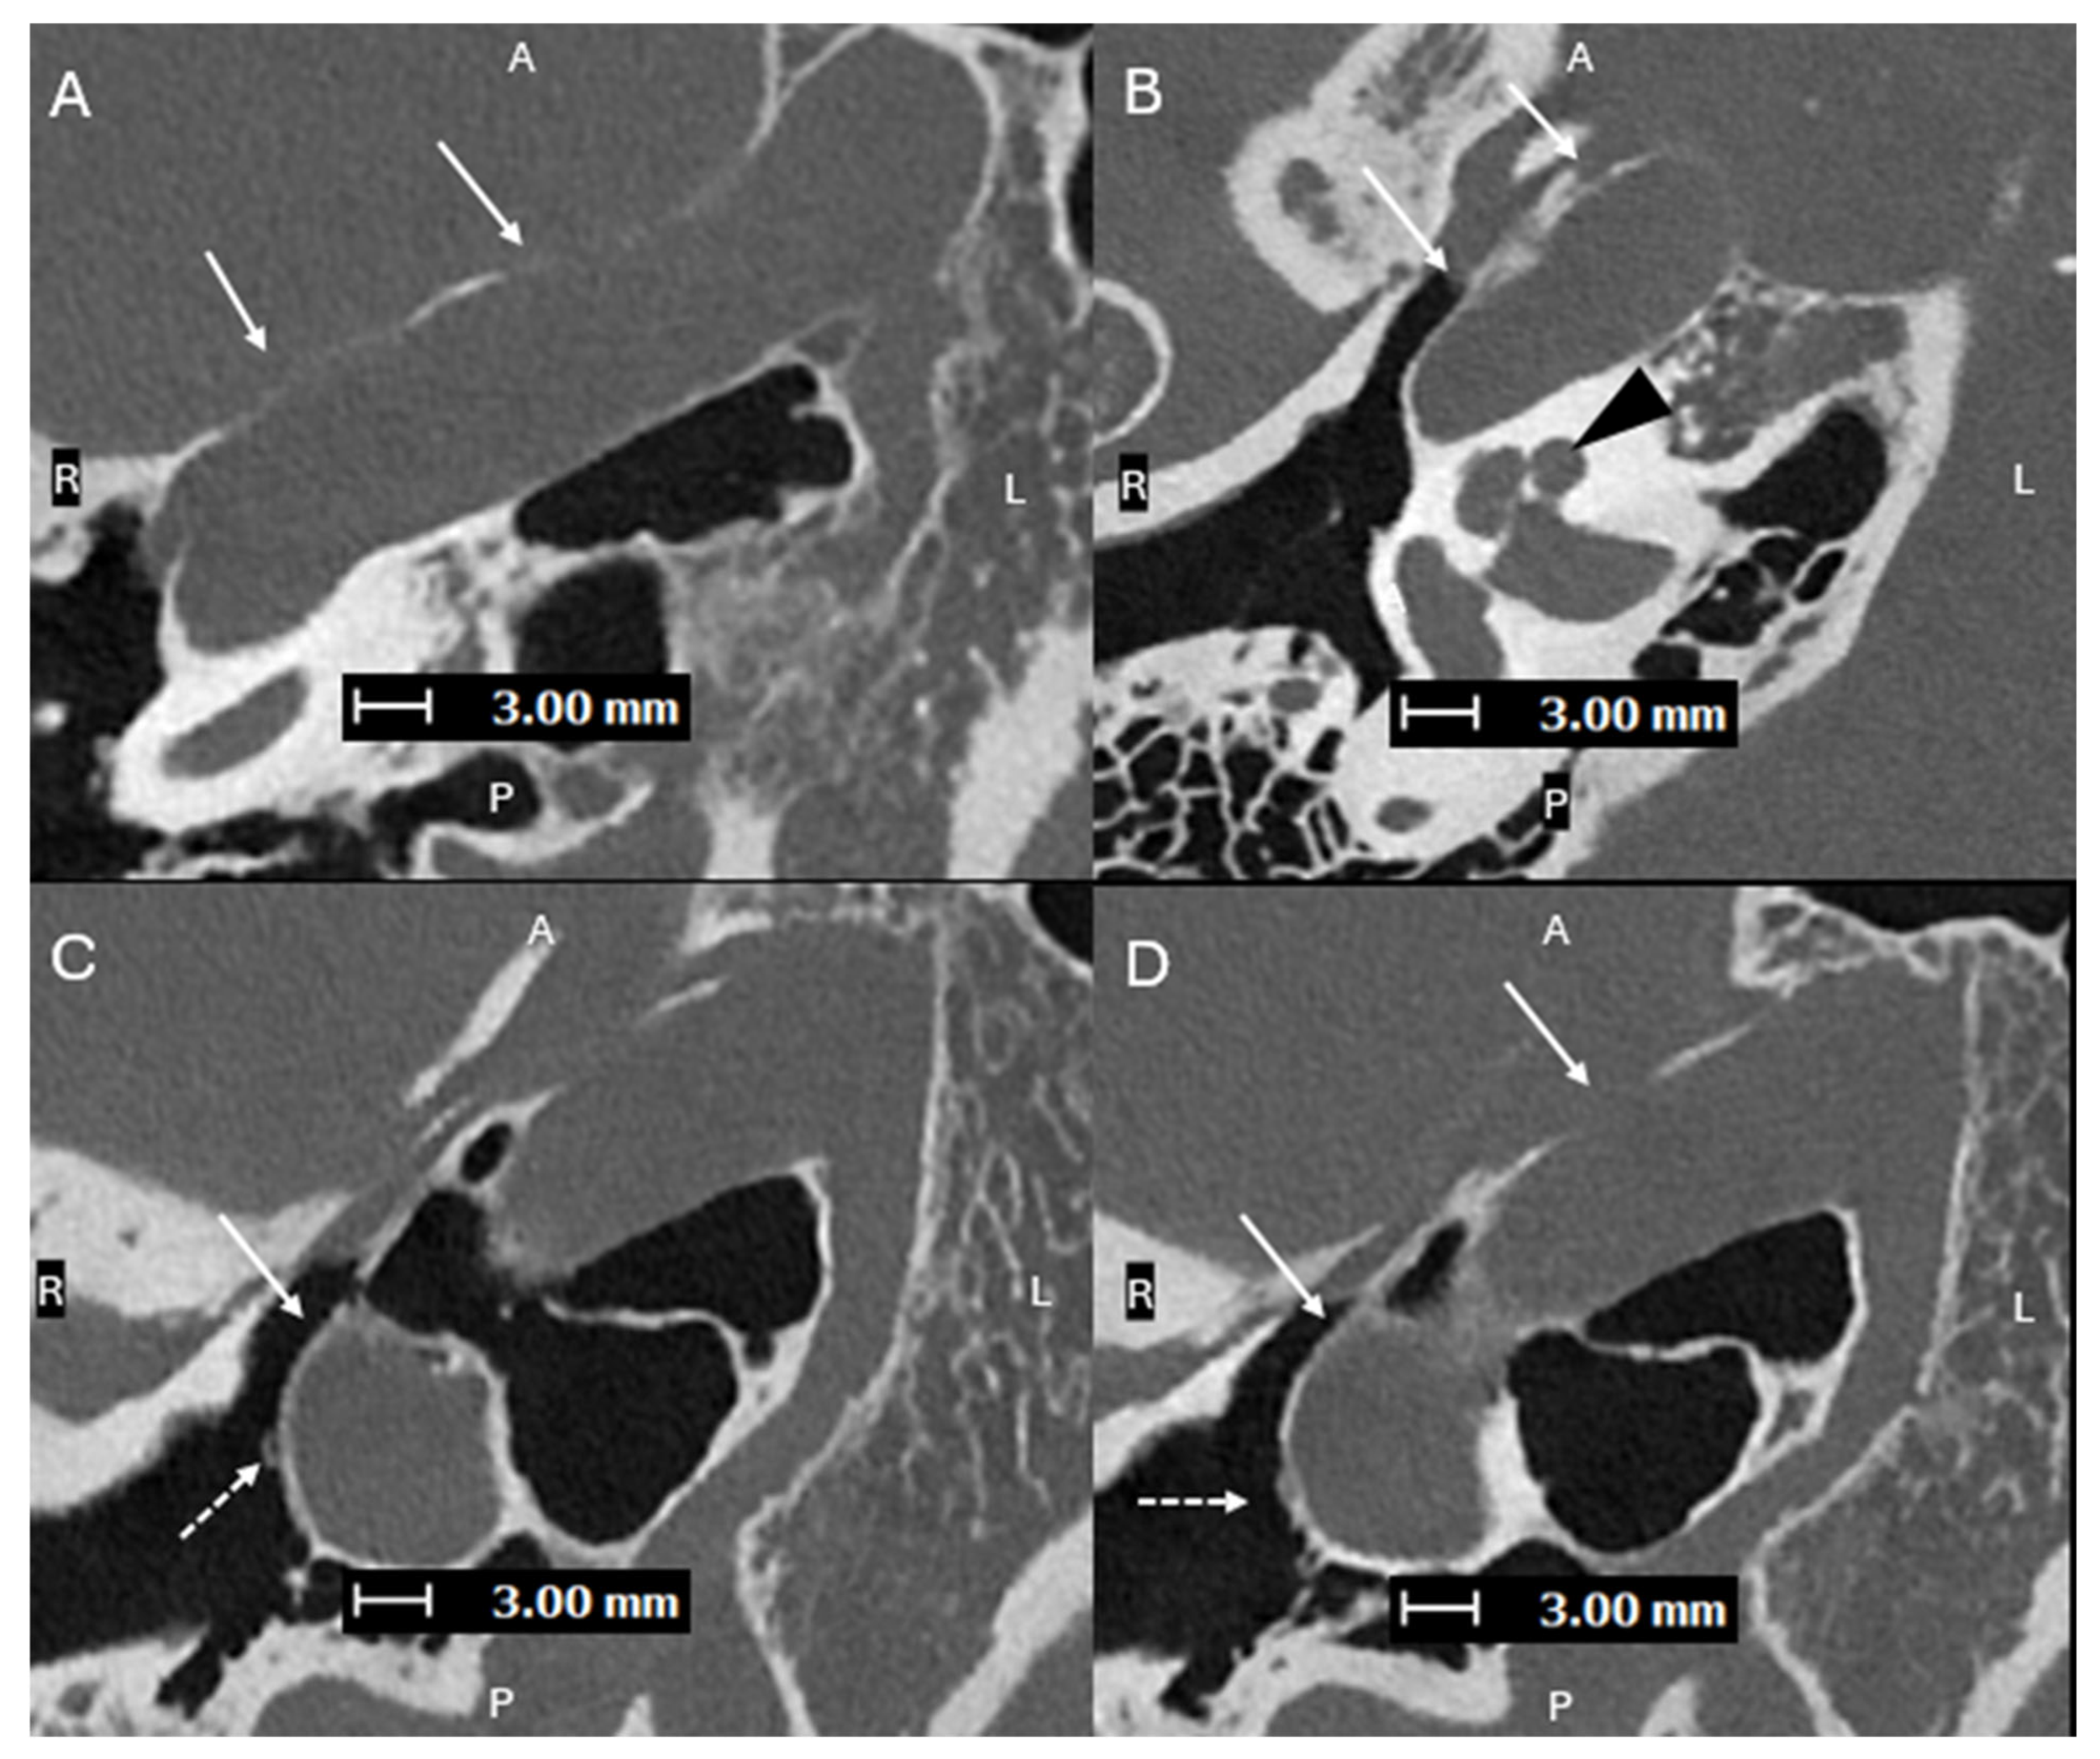

Figure 3. Axial oblique images (superior to inferior (AD), with A, P, L, R for orientation donating anterior, posterior, left, and right respectively) from a PCD-CT temporal bone study—with same acquisition and reconstruction parameters as Figure 1—demonstrating a lateralized R ICA (solid arrows). (B) shows the ICA lateral to the midportion of the basal turn of the cochlea (black arrowhead). (C,D) show the normal R ITC visualized laterally (dashed arrows), proving that this is a lateralized ICA and not an aberrant ICA. A lateralized ICA is defined as the genu of the vertical and horizontal segments of the petrous ICA positioned lateral to the midportion of the basal turn of the cochlea in the axial plane. Importantly, the ITC is not affected, which helps to distinguish a lateralized ICA from an aberrant ICA [8]. Skull base foramina, such as the inferior tympanic canaliculus, are much better seen on PCD-CT, which can greatly help when trying to differentiate between an aberrant ICA and a lateralized ICA, as shown in cases 2 and 3 [9]. On EID-CT, it can be difficult to differentiate between a lateralized ICA and an aberrant ICA.

Figure 4. Axial oblique images (superior to inferior (AC), with A, P, L, R for orientation donating anterior, posterior, left, and right respectively) from a PCD-CT temporal bone study—with same acquisition and reconstruction parameters as Figure 1—demonstrating a persistent L stapedial artery traveling inferiorly and passing through the obturator foramen of the stapes (C). (D) shows a normal foramen ovale (dashed line) with absence of the foramen spinosum, which is consistent with a persistent stapedial artery. Aberrant ICAs can be associated with a persistent stapedial artery (PSA), which is an abnormal vessel that arises from the petrous ICA and passes through the obturator foramen of the stapes [10]. The posterior division of the upper stapedial artery branch becomes the middle meningeal artery (MMA). With the normal embryologic atrophy, the distal portion of the MMA is supplied by the internal maxillary artery through the foramen spinosum. If this fails to happen, the territory of the middle meningeal artery will be supplied by the collateral connection with the ophthalmic artery or by a PSA, and absence of the foramen spinosum is expected [11]. A PSA should be recognized prior to stapes surgery. The improvement of spatial resolution with photon counting detector (PCD)-CT has been proven to provide higher performance in detection of sub-centimeter vascular lesions compared to conventional energy-integrated detector (EID)-CT [12].